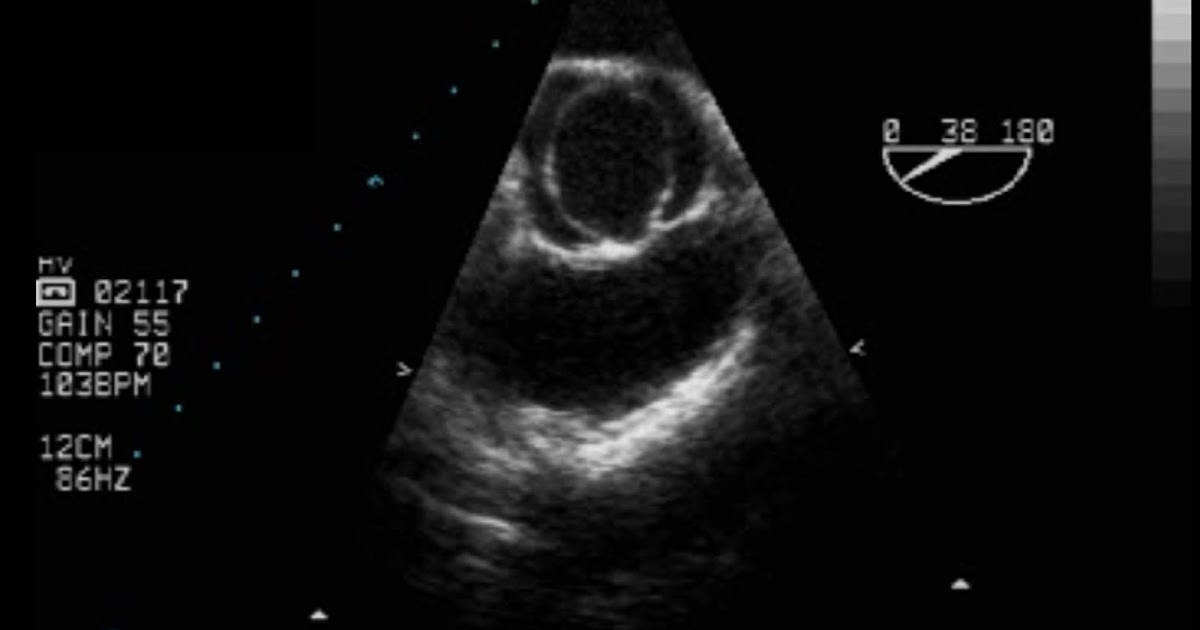

Bicuspid Aortic valve Critical Care Sonography Bicuspid Valve Dangerous However, the condition is often treatable with valve repair or replacement procedures, which can. This is when your aortic valve has only two flaps of skin (called leaflets) that help control blood. That means it is a congenital heart defect. A leaking heart valve can lead to life threatening complications. Bicuspid aortic valve the most common congenital valve problem is. Bicuspid Valve Dangerous.

Bicuspid arotic valve Disease (Echocardiography)by Babita YouTube Bicuspid Valve Dangerous Mr inderpaul birdi, an expert heart surgeon from london explains what bicuspid aortic valve disease is, how dangerous this disease is and how it’s treated. Bicuspid aortic valve is a type of congenital (present at birth) heart defect. A leaking heart valve can lead to life threatening complications. Bicuspid aortic valve the most common congenital valve problem is bicuspid aortic. Bicuspid Valve Dangerous.